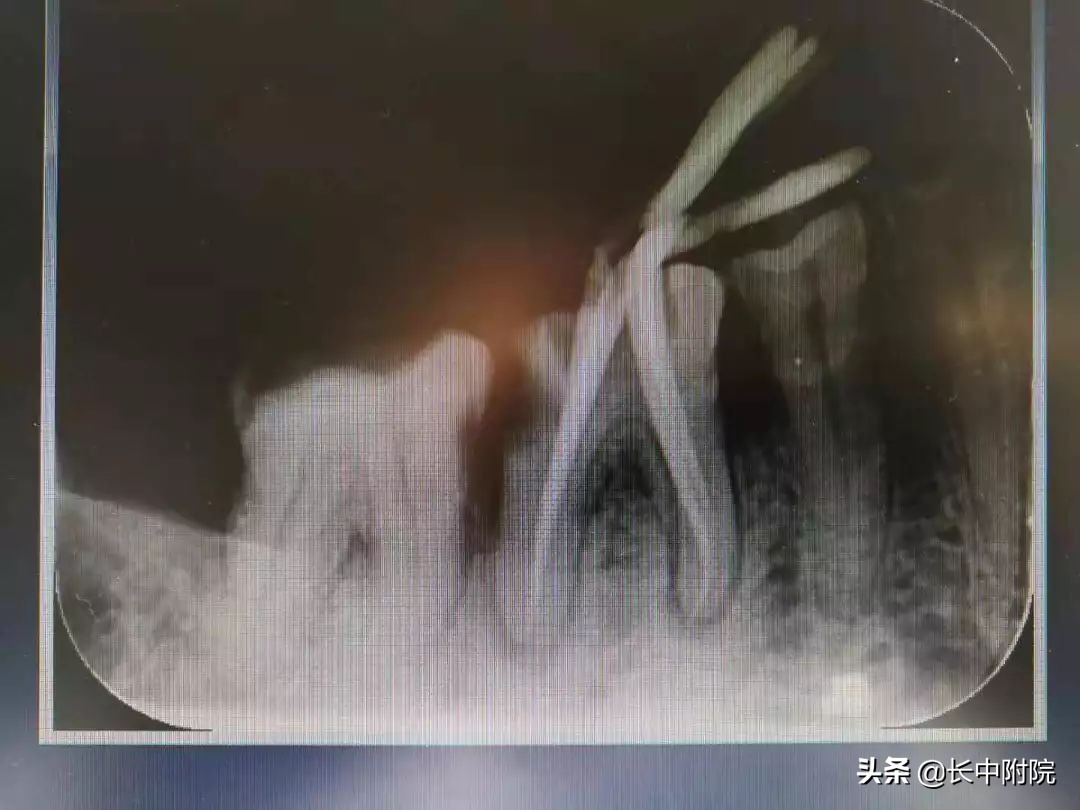

6.根管充填

封闭整个根管系统、堵塞主根管和侧副根管出口、防止微生物和液体的渗漏。无论是侧方加压法还是垂直加压法,应做到根管充填致密,根管充填后X线片上无根管腔隙,也不能超出根尖孔。

试主尖:

根管充填: